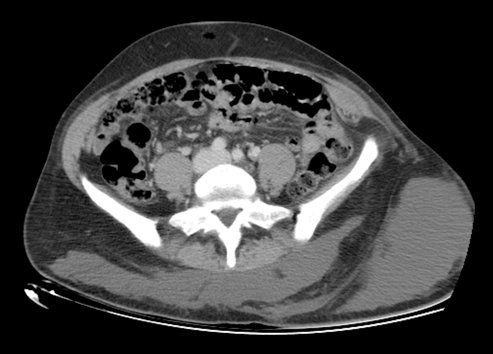

Fig. 2 Corresponde a un corte transversal de una tomografía computada, donde se puede observar en el espesor del tejido celular subcutáneo una extensa colección a nivel dorsal lumbar y en continuidad en región glútea izquierda.

El diagnóstico es clínico, aunque estudios de imagen permiten confirmar la lesión y evaluar su extensión.